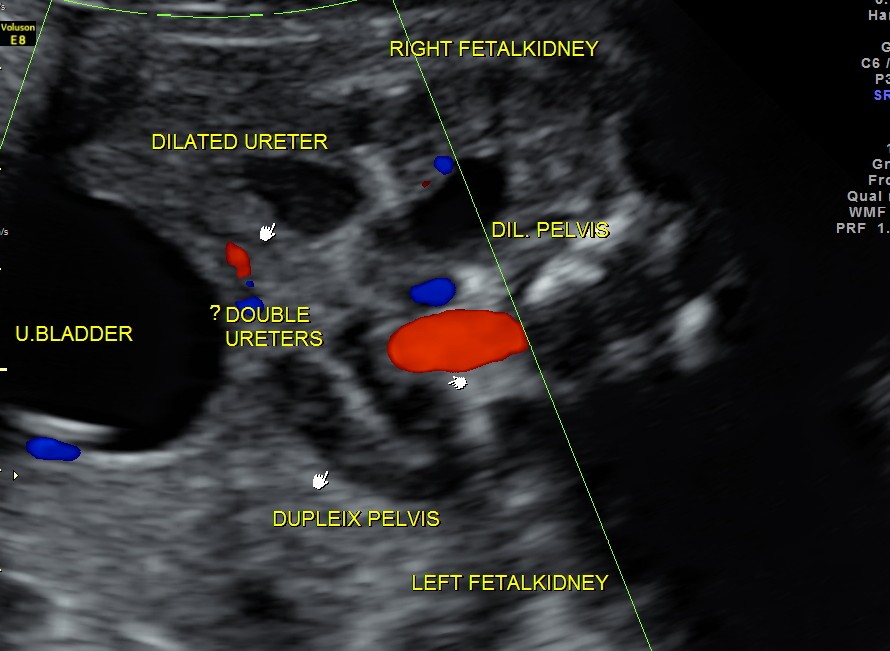

The following images show bilateral renal pelvi ectasis and bilateral dilated ureters with all the changes more in the left kidney .

The left kidney also showed possible duple-ix pelvis with double ureters arising from them . But this finding could not be confirmed in all the views .